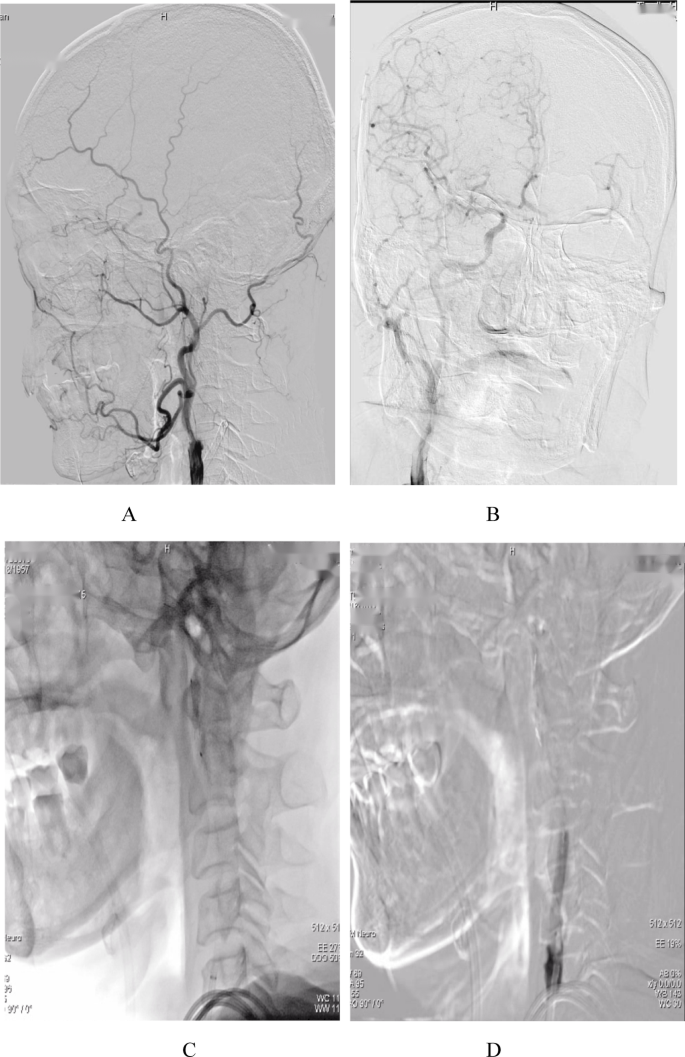

ABGCEPD (Fig. 2) was conducted after obtaining informed consent from the patients or their family members. The process was conducted as follows:

A 9 F arterial sheath was inserted into the femoral artery, and a 5 F guide catheter (Envoy; Raynham, Massachusetts, USA) was advanced. Diagnostic angiography was conducted to identify the cerebral vasculature and confirm major vessel occlusion (Fig. 2A).

A 0.014-inch microwire (Transcend; Stryker, Michigan, USA) was passed through a microcatheter (MicroVention; Tustin, California, USA) to traverse the occlusion. Simultaneously, a 9 F Balloon guide catheter (Stryker, Bayside Parkway, Fremont, USA) was inflated to obstruct the proximal blood flow.

The occlusion site was delineated by injecting a small quantity of contrast agent through the microcatheter (Fig. 2B).

Using the exchange procedure along the microguidewire, the microcatheter and microguidewire were removed. A distal embolic protection device (Spider FX; Medtronic) was inserted in the petrous segment of the ICA to prevent a big thrombus from exiting the carotid artery distally (Fig. 2C).

Balloon angioplasty was conducted at the occluded vessel using a Lite PAC 5*30 balloon, inflated to 5 to 6 atmospheres to reopen the vessel and create an endovascular path. The balloon guide catheter (BGC) remained inflated, and the distal EPD was deployed (Fig. 2D).

Continuous aspiration was applied using a large-bore catheter under negative pressure suction (Fig. 2E). Subsequently, the BCG and EPD were retrieved.

Residual thrombus from the ICA was aspirated using the large-bore catheter (Fig. 2F).

A DynaCT scan was conducted to examine the patient’s vascular status and collateral circulation. Based on the findings, a carotid artery stent was implanted under proximal occlusion14 (Fig. 2H).

A schematic diagram of the ABGCEPD technique. (A) Digital subtraction angiography (DSA) shows isolated cervical internal carotid artery occlusion. (B) Inflating BGC to occlude the proximal blood flow, a microcatheter traveling through the occlusion site with the assistance of a microwire. (C) An embolic protection device was advanced into the distal cervical segment of the ICA over the microwire. (D) Balloon angioplasty of the initial ICA segment. (E) The BGC is advanced to the bulb portion to secure ICA flow arrest. (E) After removing the angioplasty balloon, continuous aspiration can be performed until there is profuse backflow through the occluded BGC. (F) Inflate the BGC to occlude proximal blood flow while continuous aspiration throughout the procedure using large-bore catheter. (G) Using the BGC to occlude proximal blood flow, and then an internal carotid artery stent is inserted.